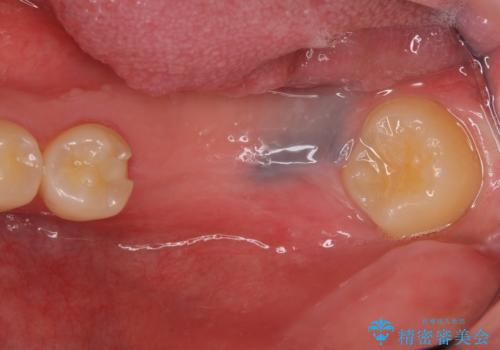

カスタムアバットメントは患者様それぞれの歯茎に合わせて製作されたオーダーメイドのアバットメントです。

既製のアバットメントに比べ適合がよく、高い清掃性を誇ります。